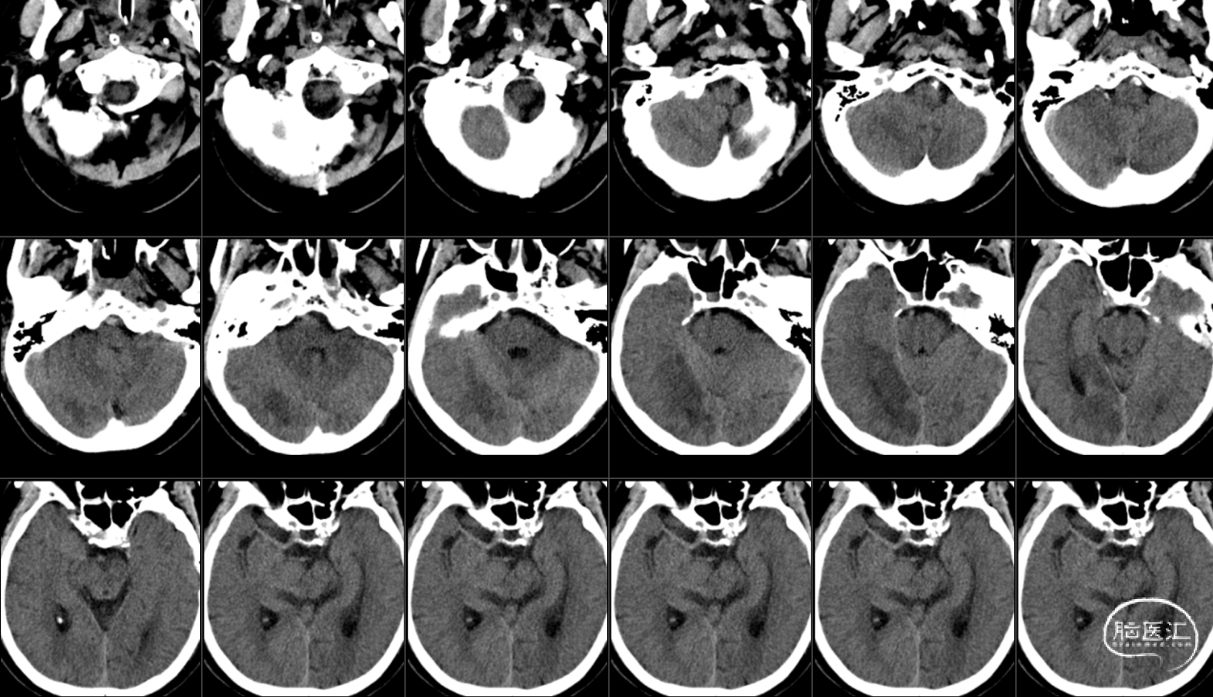

复查颅脑CT(术后1天)